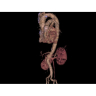

Компьютерный томограф GE Brivo CT385 представляет собой современное диагностическое оборудование, сочетающее высокую точность исследований с повышенным комфортом для пациентов. Этот аппарат открывает новые возможности для детальной визуализации анатомических структур.

Позволяет проводить комплексные исследования всех анатомических зон, включая нейровизуализацию, ангиографию, исследования органов грудной и брюшной полости. Особенно эффективен для раннего выявления онкологических заболеваний.

Специализированные исследования

Обеспечивает высокую точность при кардиологических исследованиях, визуализации костных структур и суставов. Подходит для динамического наблюдения в ходе лечения.